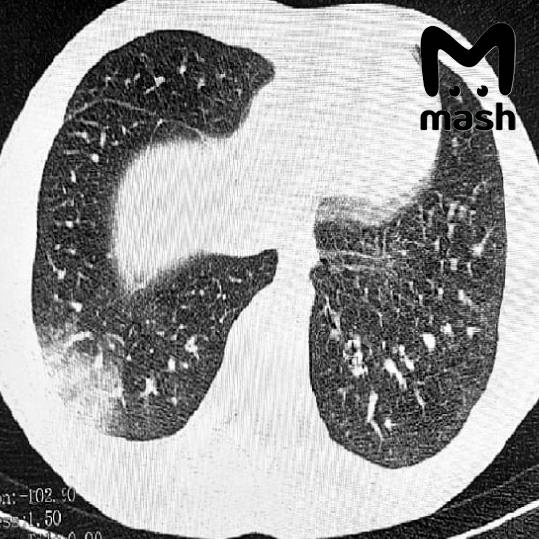

Троих зумеров экстренно доставили в реанимацию Ростовской области с попкорновой болезнью лёгких

Троих зумеров экстренно доставили в реанимацию Ростовской области с попкорновой болезнью лёгких — которая развилась из-за постоянного курения вейпов. Подростки в тяжёлом состоянии, одному пришлось делать операцию на лёгких. У 16-летнего пациента — серьёзная дыхательная недостаточность, потребовалась искусственная вентиляция лёгких. У другого — двусторонняя вейп-ассоциированная пневмония EVALI, врачи сделали операцию. Похожие случаи фиксируют и в других регионах России: первые в Москве в 2021-м, затем в Томске, где в прошлом году пострадали двое несовершеннолетних. Врачи говорят: электронки серьёзно портят здоровье. Жидкости в дуделках содержат химические вещества, которые повреждают дыхательные пути, вызывают воспаление лёгких и приводят к проблемам с дыханием.